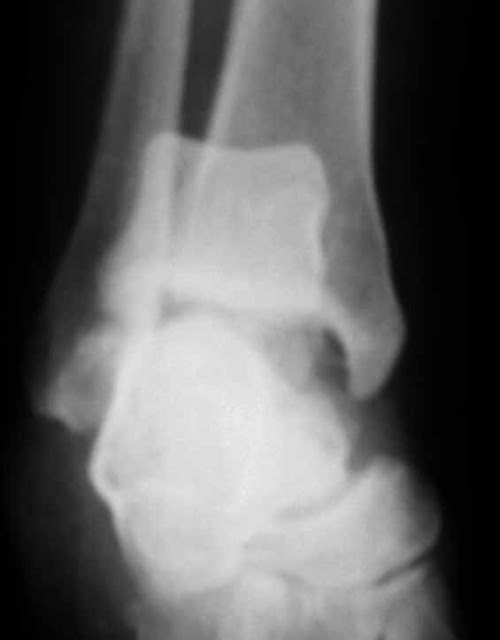

RXS SE MUESTRAN A CONTINUACIÓN.

DX FRACTURA DE

CLAVICULA IZQUIERDA

ALLMAN TIPO

III